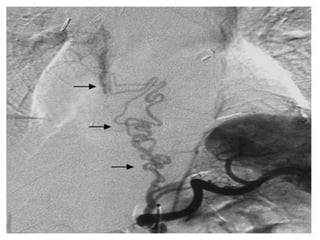

Pathologic Features Of

The Bronchial Artery

Non-bronchial

Systemic

Artery

Anatomy

brachiocephalic arterythe aortic arch

internal mammary

Pericardiacophrenic

subclavian artery

thyrocervical trunk

(Yoon et al., 2002)

Non-bronchial Systemic Artery Anatomy brachiocephalic arterythe aorticarch internal mammary artery Pericardiacophrenic subclavian artery thyrocervical trunk (Yoon et al., 2002)